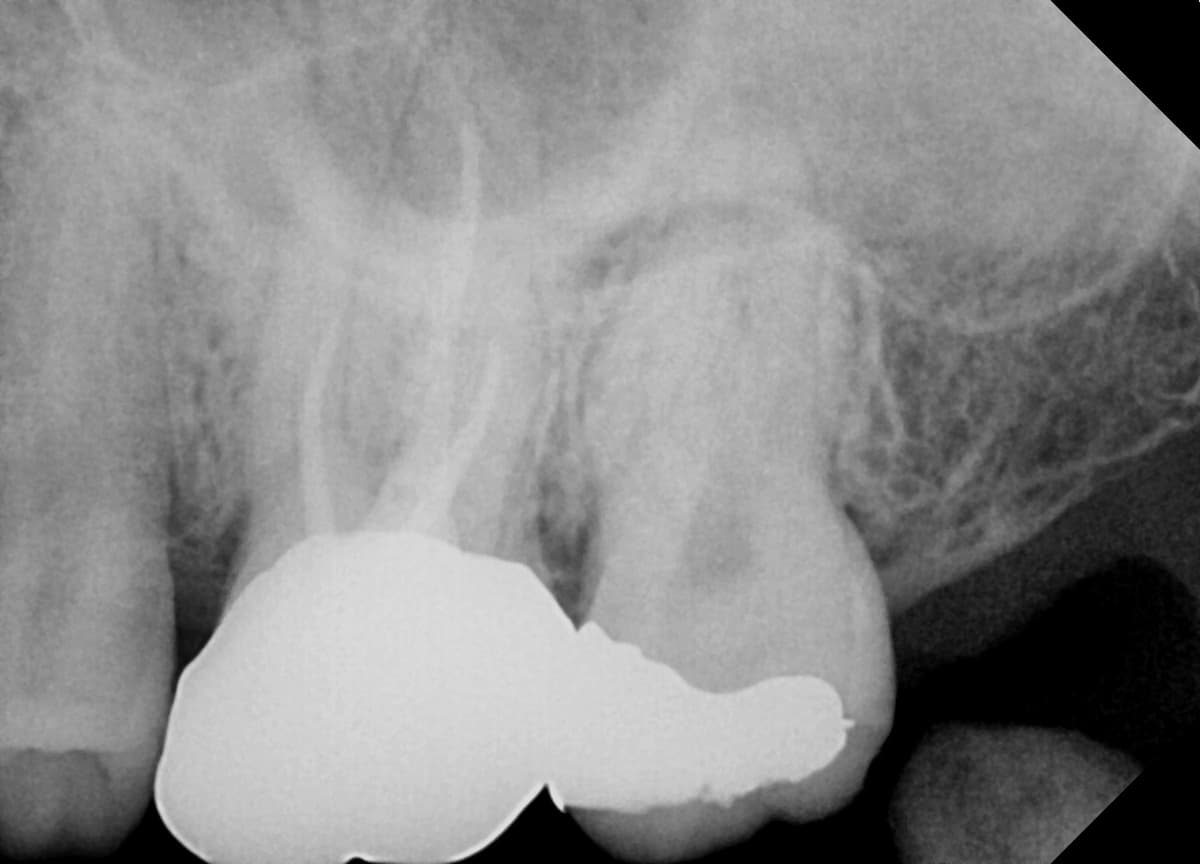

치근단병소 치유

뿌리 끝 염증으로 발치 권유받은 어금니

Before

After

신경치료 1년 2개월 후 치근단병소 완전 치유